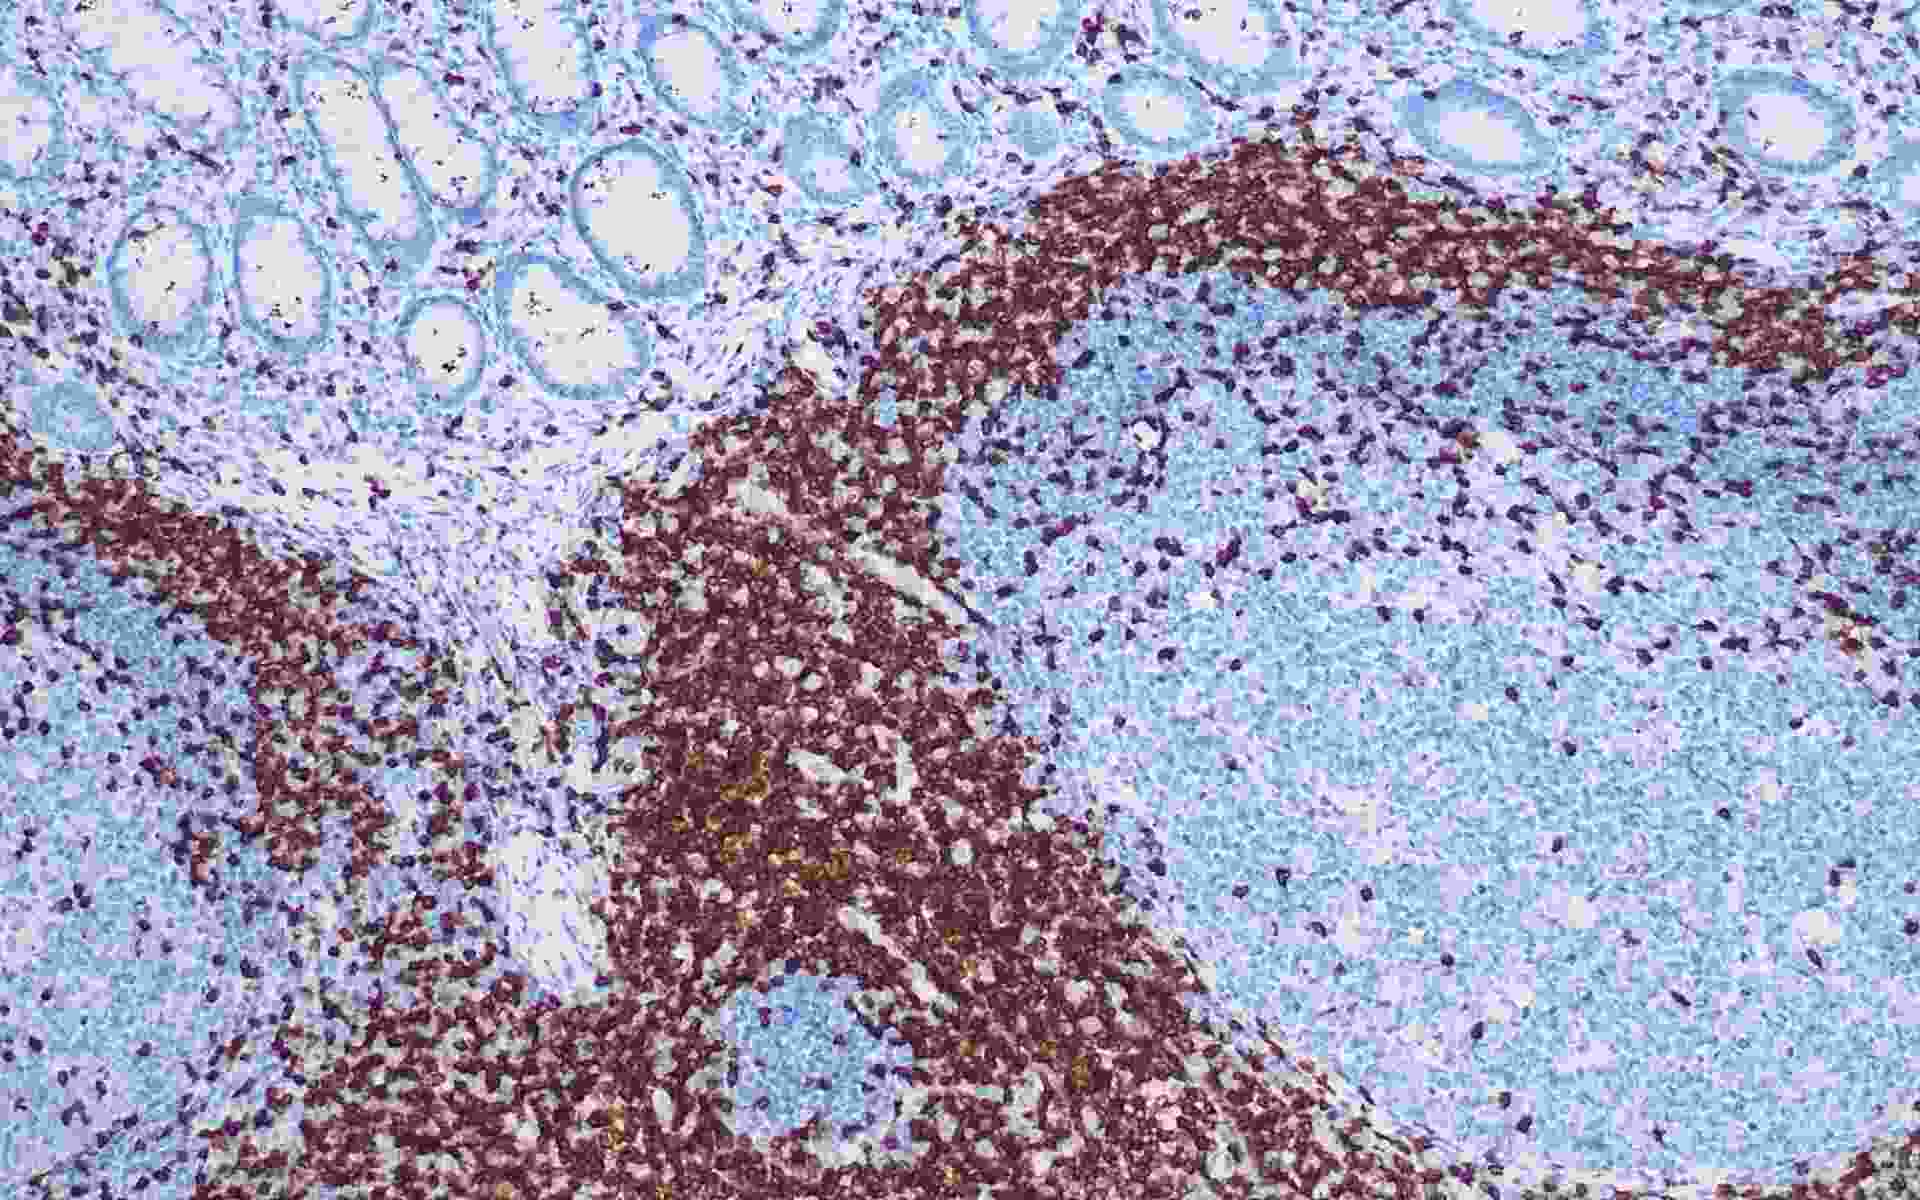

• CD3阑尾(T细胞)

CD3是由4个结构不同的膜糖蛋白异构体组成,表达于所有T细胞表面,是目前认为最能代表T细胞的标记抗体。 CD3可与由α/β或γ/δ组成的异源二聚体(TCR)形成复合受体分子,是T细胞识别抗原的主要单位,具有稳定TCR结构和传递活化信号的作用。CD3是T细胞和NK细胞的标记物,常用于此类淋巴瘤的分类。在小脑的浦肯野氏细胞有微弱表达,在B淋巴细胞、巨噬细胞、髓细胞或者其他细胞不表达。